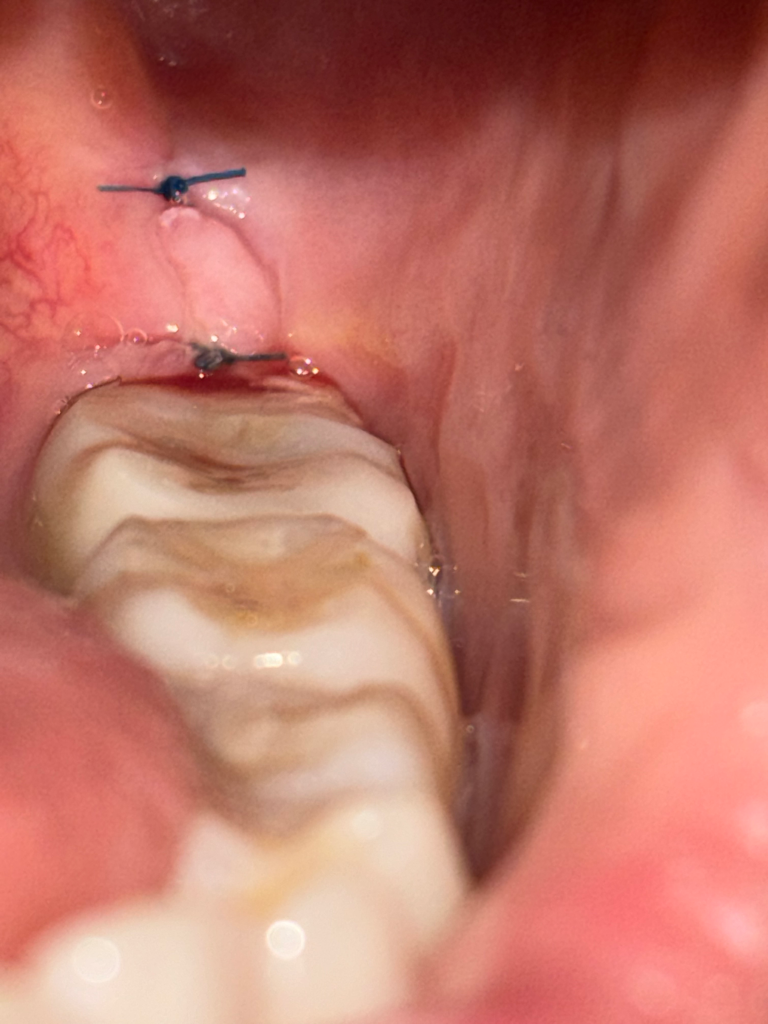

매복사랑니 발치 4일차 꼬맨곳이 약간 벌어진거 같아요

매복사랑니 발치한지 4일차인데, 약간씩 피가 나고 꼬맨곳이 조금 벌어진거같고. 실이 살에 묻한거 같은데 괜찮을까요? 설날이라 월욜까지 치과 갈 시간도 없는데 드라이 소켓이 생기는거 아닌지 걱정이 되네요.

사진상으로 보면 문제가 잇어 보이진 않습니다. 드라이 소켓은 아닌거 같으니 너무 걱정하지 않으셔도 될것같습니다 .

사진상 특별히 문제가 될 것은 보이지 않습니다. 드라이소켓은 음주, 흡연 안하시면 괜찮습니다.

외견상 봉합은 비교적 잘 되어 있는 상태입니다

사랑니 발치 후 출혈은 일주일정도까지도 소량은 있을 수 있습니다

사진을 아주 잘 찍으혔네요. 정상적으로 잘 아물고 있어 보입니다.

사진으로만 봤을 경우에는 잇몸이 잘 봉합되어 있고 잘 아물고 있는 것으로 보입니다 드라이 소켓이 생길 가능성은 매우 적으니 너무 걱정하지 않으셔도 됩니다.

현재 사진상으로는 크게 문제가 되어 보이지 않으며, 피가 조금씩 묻어날수는 있습니다. 묻어나는 피는 벧지말고 삼키길 권합니다.